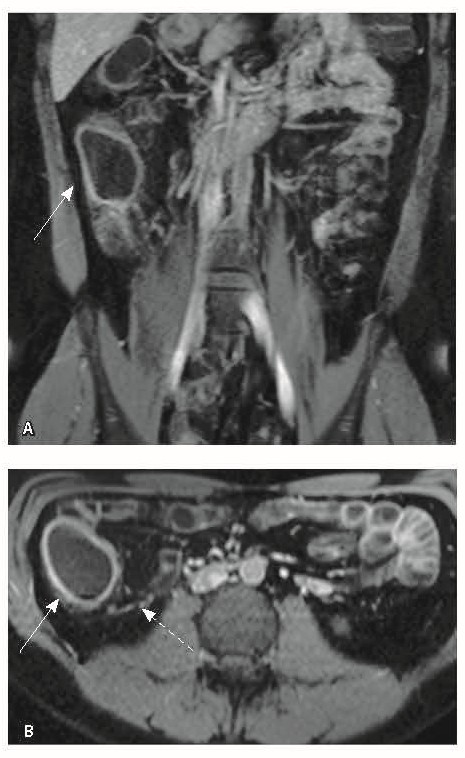

Назначена ГИБТ адалимумабом (препарат Хумира) по стандартной схеме 160 мг п/к (неделя 0), 80 мг п/к (неделя 2) с последующим плановым поддерживающим режимом 40 мг п/к каждые 2 недели. Через 9 месяцев установлена эндоскопическая ремиссия, однако сохранялась концентрация фекального кальпротектина более 2000 мкг/г. Через год жалобы возобновились, тогда же впервые была выявлена задняя анальная трещина. Выполнена магнитно-резонансная энтерография, обнаружены воспалительные изменения, характерные для БК (рис. 2 и 3).

Рис. 2. Магнитно-резонансная энтерография, Т2-взвешенное изображение: А, В – фронтальная проекция; Б – аксиальная проекция. Наблюдается отсутствие гаустрации в восходящем отделе ободочной кишки, утолщение ее стенки до 5 мм (стрелка), снижение магнитно-резонансного сигнала от прилежащих отделов клетчатки, ее неоднородность (пунктирная стрелка), увеличение лимфатических узлов до 6 см в диаметре по ходу сигмовидной кишки (стрелки)